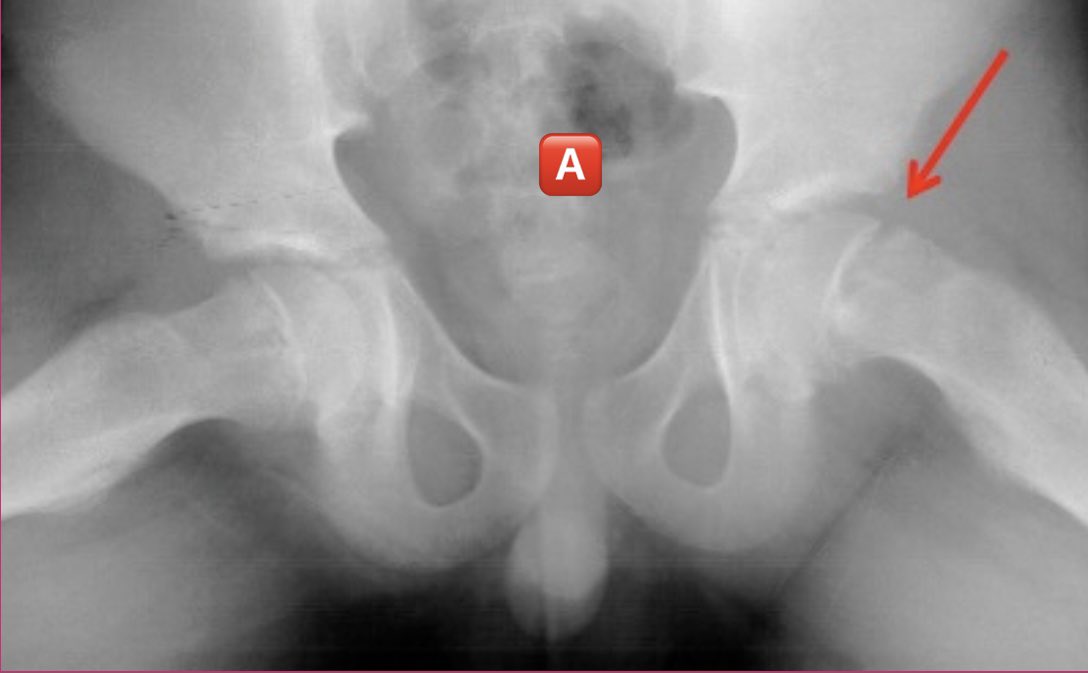

الصوره 🅰️ اول ما وصل الولد للمستشفى،، الصوره 🅱️بعد زياره العشاب وباين ان حالته أسوأ